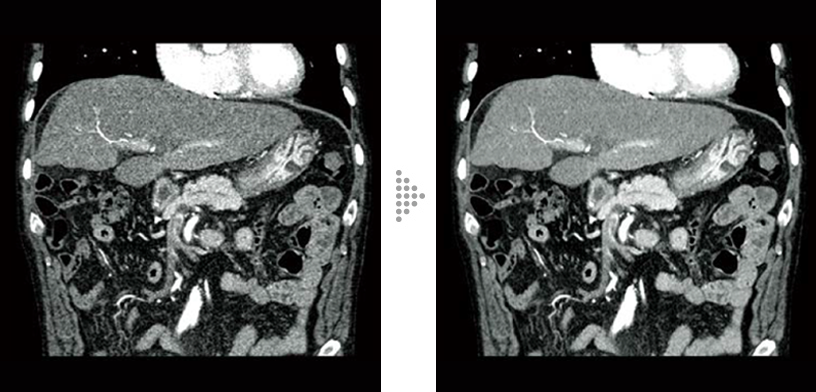

FBP(Left)

Intelli IPV(Right)

Abdominal aortic occlusion